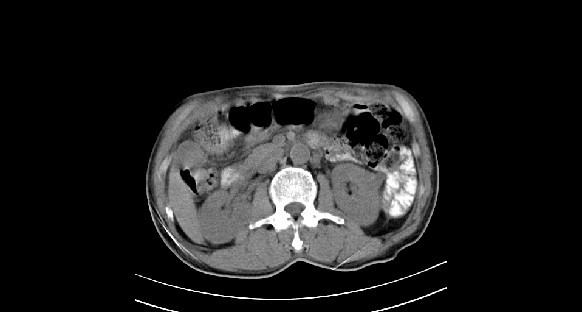

男性,70岁,体检b超发现左肾占位,请各位战友发表一下观点

左肾有两个病灶,且较大的病灶内可见点状钙化灶,增强扫描边缘也是呈渐进性强化,中央部分未见明显强化